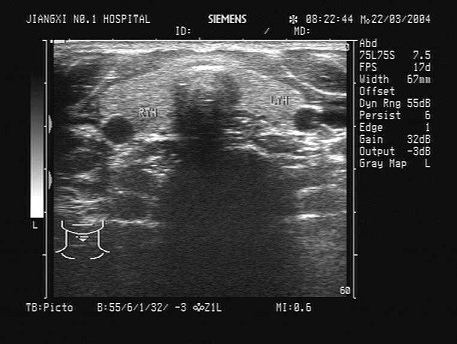

如图,正常甲状腺中部横切面的超声声像图,中央气管环状软骨前方组织为( )

A:甲状腺峡部

B:皮下组织

C:甲状旁腺

D:淋巴结

E:以上均不对